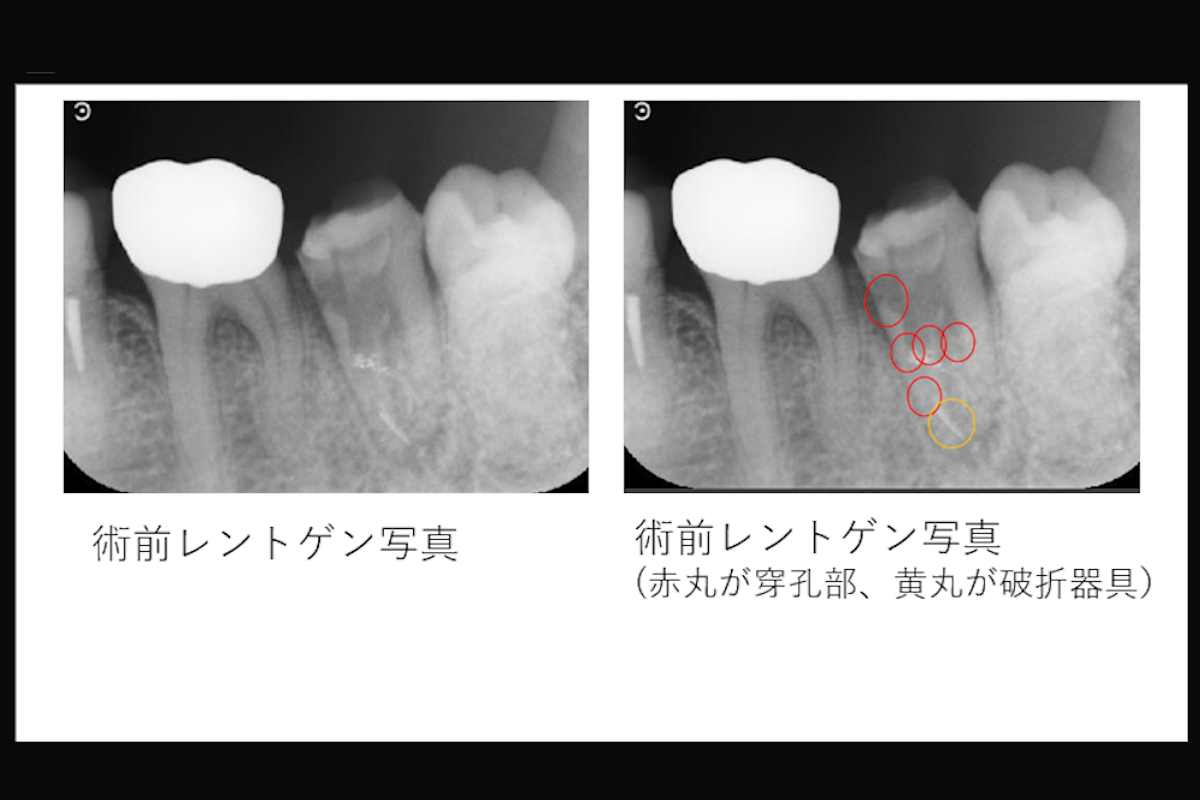

【5ヵ所の穿孔と根尖部の破折器具を伴う下顎左側第二大臼歯の症例】「近医で抜歯と言われたが、歯を残したい。」

- 5ヵ所の穿孔と根尖部の破折器具を伴う下顎左側第二大臼歯の症例

- 治療内容:下顎左側第二大臼歯 根管治療(破折器具の除去、MTAを用いた根管充填)